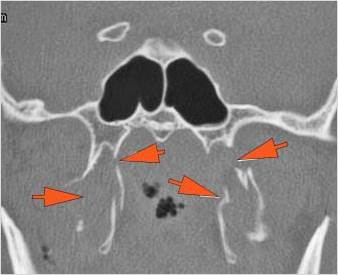

There is localized edema, hematoma or abscess within in the facial or scalp soft tissues, SMAS, infratemporal fossa, masticator space or oral cavity.

There is evidence of gas or a foreign body at a possible fracture site, indicative of an open or penetrating injury.

There is soft tissue swelling suggesting injury to the parotid or submandibular glands.

There is bony injury of the body, alveolar ridge, premaxilla, the infraorbital rim, the palatine or the frontal process of the maxillary bones on either side.

There is bony injury or displacement of the body, angle, ramus, alveolar ridge, condylar coronoid process and parasymphyseal or symphyseal region of the mandible.